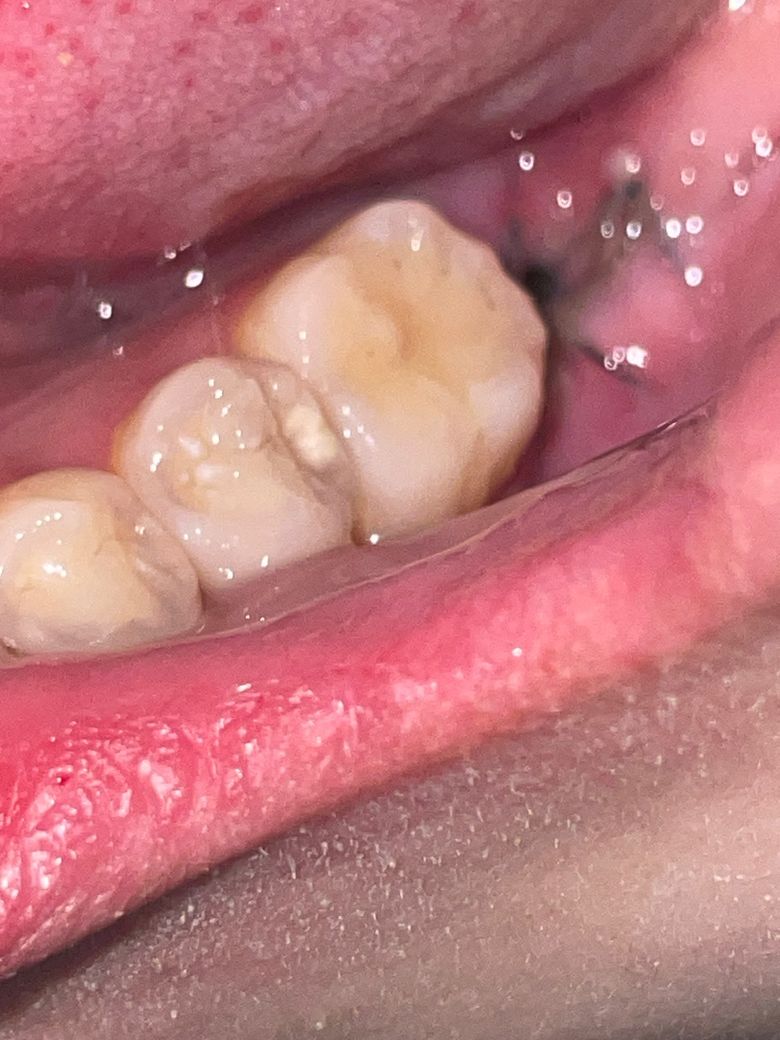

드라이소켓의심 질문자 입니다 . +사진 확인 도와주세요

그리고 침을 삼키는데 쓴맛이라기엔 묘한 이상한 맛이 약하게 납니다. 그리고 침을 삼킬 때 수술 부위쪽 볼이 그쪽으로 쏠리는? 느낌도 납니다. 통증은 약먹으니 줄어들었는데 앞 어금니가 욱씬거리는 통증이 동반되었었습니다. 오른쪽 다리가 갑자기 열감이 느껴지기도 하구요. 드라이소켓이 염증반응이 있어 열과 통증이 있다고 해서 너무 걱정됩니다ㅠㅠ

• 2번 째 사진

드라이소켓의 양상 아닙니다 발치 후 저정도 구멍 있는건 지극히 정상입니다 구멍이 온전히 메워지기 위해서는 한달이상 걸립니다

원래 치아 발치후에는 발치한 자리에 이정도의 구멍은 생깁니다. 통증이 더 심해지면 치과로 도로 가서 확인하고 필요한 치료해야 합니다. 사진으로 보기에는 드라이소켓 같지는 않습니다.

발치하신지 3-4일정도지낫는데 냄새도 나고 통증이 잇다면 드라이 소켓일 가능성이 잇으니 치과에 가셔서 소독을 한번 받아보시는게 좋을것같습니다.